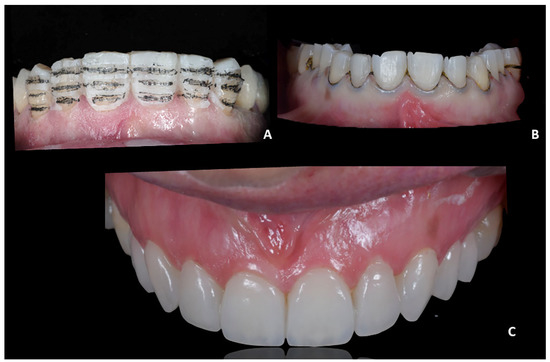

Orthodontic set-up. The orthodontic treatment aimed to optimize the position of 2.1 and 2.2 using clear aligners. In the Clincheck software, the linguo-vestibular inclination of the 2.1 and 2.2 were corrected using the position of the temporary elements (i.e., 11 and 12) as the anatomical limit for the orthodontic movement. The programmed orthodontic movement was staged, and seven aligners were required to achieve the final pre-prosthetic teeth position. The patient wore each aligner for 2 weeks for a total treatment time of 14 weeks (Figure 12). During the therapy with systematic Invisalign GO, dynamic compression of the soft tissues was performed in both the pontic region and the intra-mucosal region (Figure 13).

Figure 12. Case 2. Orthodontic set-up. (A) pre-treatment; (B) simulated final position of 2.1 and 2.2 using the position of 1.1 and 1.2 as references.